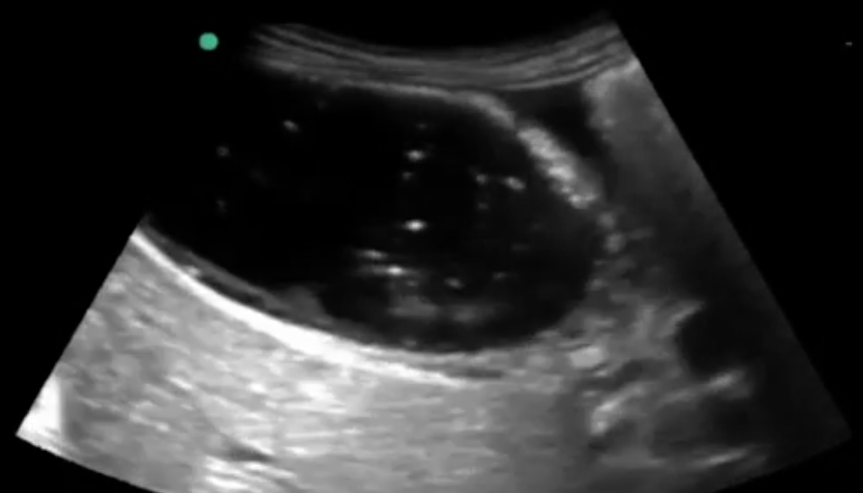

Gallbladder Cholecystitis Image